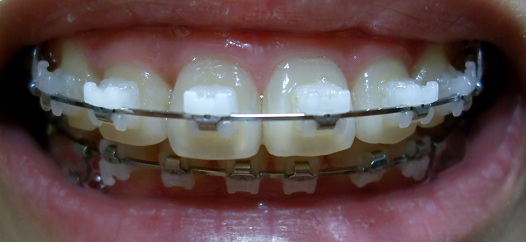

우와. 세라믹교정보다 뭔가 더 깔끔한 느낌이에요!

똑딱이교정 중이신걸로 알아용 ^_~

(부러우면 지는거 지는거 ㅠㅠ)

감사합니당ㅎㅎㅎㅎㅎ 장치가 치아색이랑 비슷하게 희어서 더 깔끔해 보이는거 같아요~